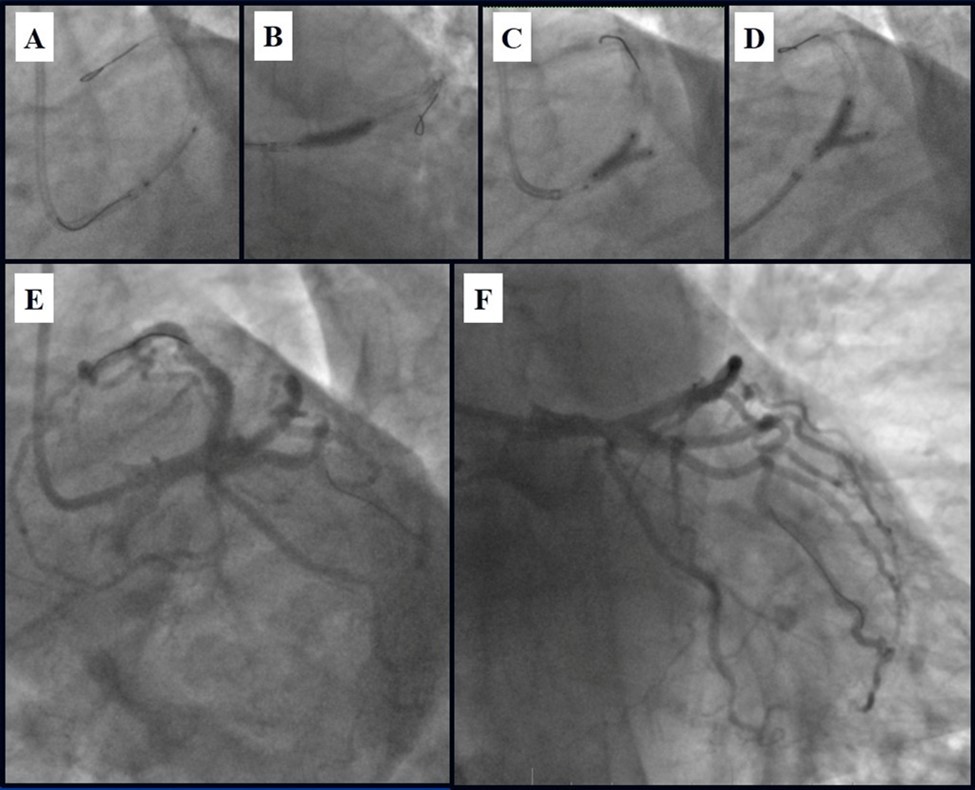

Angiography revealed rare anatomical variation LMCA quadrifurcation (Figure 1, Figure 2), 50% stenosis of the distal part of the LMCA, 40% stenosis of the ostial segment of left anterior descending (LAD) artery and diffuse prolonged 70-75-95% stenosis in mid-segment (Figure 3), 75% stenosis of the ostial segment of the circumflex (CX) artery, 75% stenosis of the ostial segment of the first marginal branch (OM1), 75-90% stenosis of the proximal segment of the intermediate artery (IMA), prolonged diffuse severe 90-95% stenosis of mid-segment of the right coronary artery (RCA) (Figure 4).

Figure 1.Quadrifurcation of the left main coronary artery

Quadrifurcation of the left main coronary artery

In the first stage, despite the fact that BMS is contraindicated in diabetic patients, RCA was stented with 3 bare-metal stents (BMS) (Rebel, Boston Scientific) (due to financial problems - drug-eluting stents was not covered by insurance). We used BMS to have at least temporarily patent RCA during LMCA stenting (Figure 5) (we believe that, when RCA is functional, LMCA stenting is safer). LAD was stented with 2 drug-eluting stents (Resolute Integrity, Medtronic). After the first PCI patient’s symptoms were relieved (Figure 6).

Figure 5.A, B, C - Stenting of the RCA with BMS; D - Angiography result.

A, B, C - Stenting of the RCA with BMS; D - Angiography result.

Figure 6.A, B - Stenting of the LAD with DES; C - Angiography result.

A, B - Stenting of the LAD with DES; C - Angiography result.

Figure 10.Stenting of the LMCA quadrifurcation: A, B - balloon modified mini crush stenting of the IMA, C - angiography result, D,E - modified balloon crush stenting of the CX-OM1, F - angiography result.

Stenting of the LMCA quadrifurcation: A, B - balloon modified mini crush stenting of the IMA, C - angiography result, D,E - modified balloon crush stenting of the CX-OM1, F - angiography result.

Figure 11.Stenting of the LMCA quadrifurcation: A, B – Stenting of the LMCA; C –Kissing balloon post dilatation of the IMA-LMCA-LAD; D - Kissing balloon post dilatation of the CX-OM1-LMCA; E, F - angiography result.

Stenting of the LMCA quadrifurcation: A, B – Stenting of the LMCA; C –Kissing balloon post dilatation of the IMA-LMCA-LAD; D - Kissing balloon post dilatation of the CX-OM1-LMCA; E,                             F - angiography result.